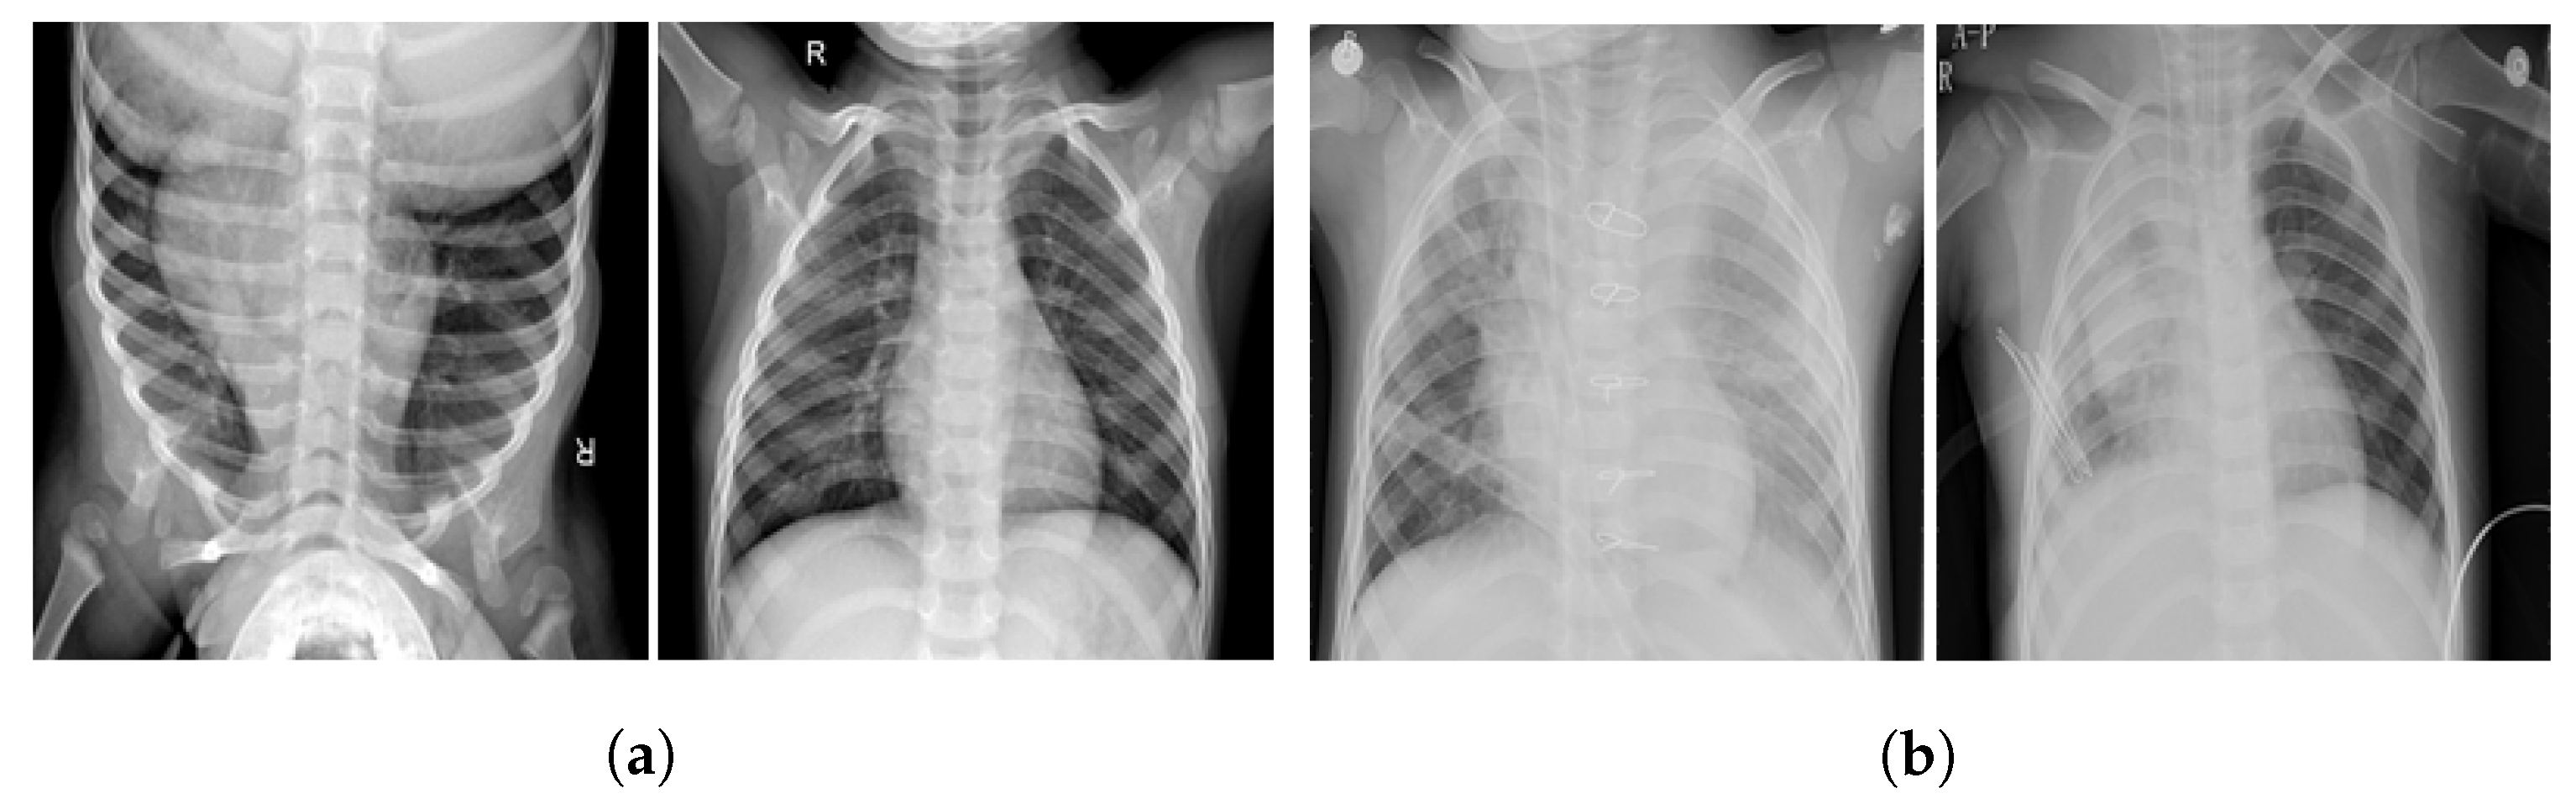

The purpose of the data augmentation is to balance the class distribution so as to improve the training process of the models, thereby enhancing their performance. A few sample X-ray images of normal and pneumonia classes are shown in Figure 2.

Figure 2. Samples of CXR images. (a) Normal and (b) pneumonia.